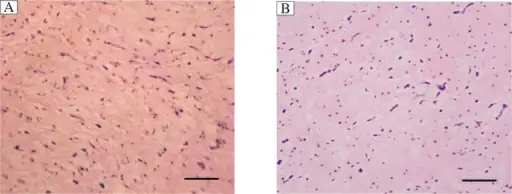

Rhabdomyomas are benign hamartomas of cardiac muscle.

Rhabdomyomas are the most common type of cardiac tumors in children.

Patients with tuberous sclerosis are at increased risk of rhabdomyomas.